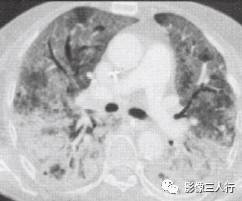

非典型肺炎的CT征象特点:分布不均匀、形态不同、大小不一的肺实变是本组 患者共同存在的基本CT表现。肺实变通常由于肺泡内充盈浆液性、渗出性或血性液 体、炎细胞或其他成分,导致肺实质弥漫性或局灶性密度增高。早期表现为边界不 清楚的0.5〜1.0cm的结节性高密度灶,随着病变的进展,融合成团块或斑片状阴 影,掩盖肺血管纹理。较大的实变影像内可见支气管分支的透亮影则为空气支气管征。见图9。